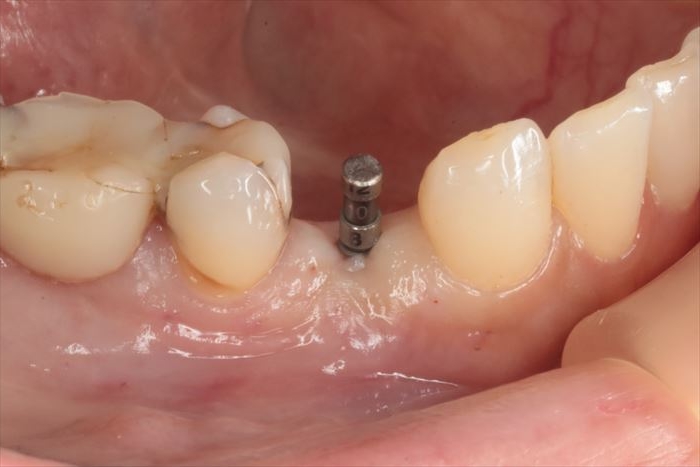

埋入トルクは十分なことから6週後に仮歯を作成して噛めるようになります。

インプラントのネック部分をカバーするように粘膜を寄せて縫合しています。

仮歯作成時にはCO2レーザーを照射して余分な歯肉を蒸散します。

インプラント埋入から6週後の状態です。(2025.10.24)

CO2レーザーで歯肉を蒸散してインプラントのマージンを露出させます。